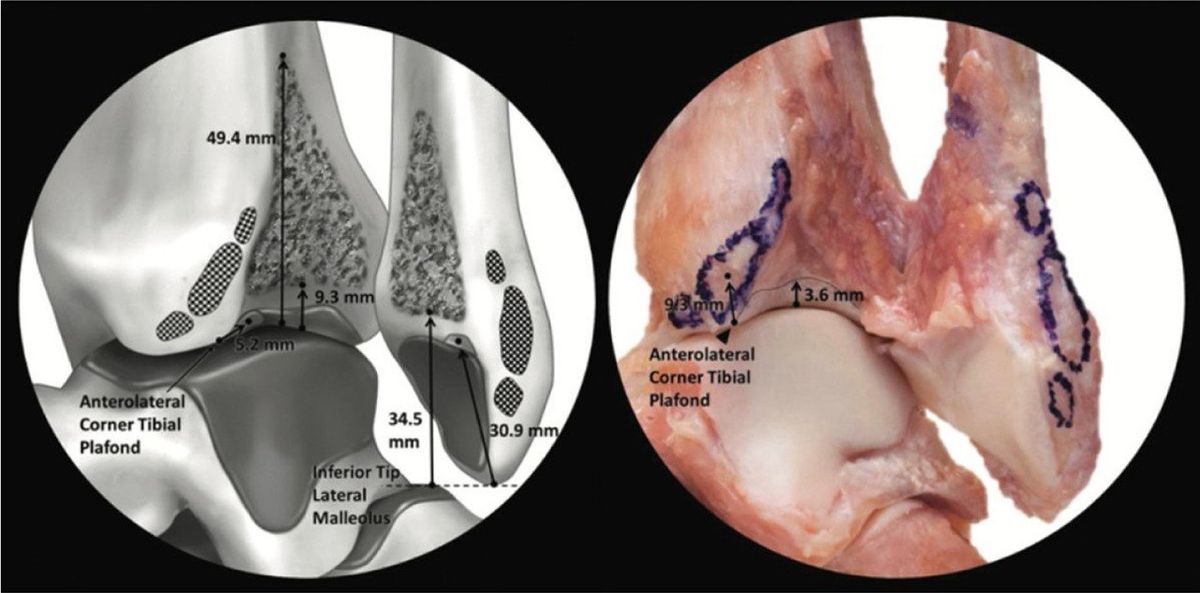

Межкостная мембрана и межкостная связка

Межкостная мембрана проходит между большеберцовой и малоберцовой костями на всём их протяжении. В самом дистальном отделе она утолщается и формирует пространственную сеть пирамидальной формы, заполненную жировой тканью и крутыми пучками волокон, которые образуют межкостную связку. Большинство волокон идут от большеберцовой кости латерально-дистально и кпереди к малоберцовой кости, хотя некоторые волокна на передней поверхности имеют обратное направление.

Наиболее дистальные волокна прикрепляются к большеберцовой кости на уровне переднего бугорка и спускаются прямо к малоберцовой кости чуть проксимальнее таранно-большеберцового сустава. Наиболее проксимальные волокна прикрепляются к большеберцовой кости у верхушки вырезки. Межкостная связка отличается значительной вариабельностью: у одних людей она отсутствует, у других — отчётливо выражена, особенно при уплощённой вырезке большеберцовой и малоберцовой костей. Область под межкостной связкой обычно занята синовиальной складкой из таранно-большеберцового сустава.

Рис. 9. Большеберцово-малоберцовая межкостная связка (БММС/TFIL). Пирамидальная форма. Площадки прикрепления: малоберцовая кость — 70,4–34,5 мм от верхушки, большеберцовая кость — 49,4–9,3 мм от переднелатерального угла. 3D-модель и кадаверный препарат.